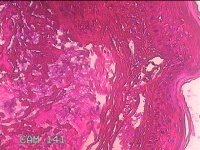

声带新生物

性别

男

年龄

29岁

临床诊断

声带息肉

一般病史

声嘶1月余。

标本名称

声带肿物

大体所见

灰白粉红色小米大组织一块。

良性病变。